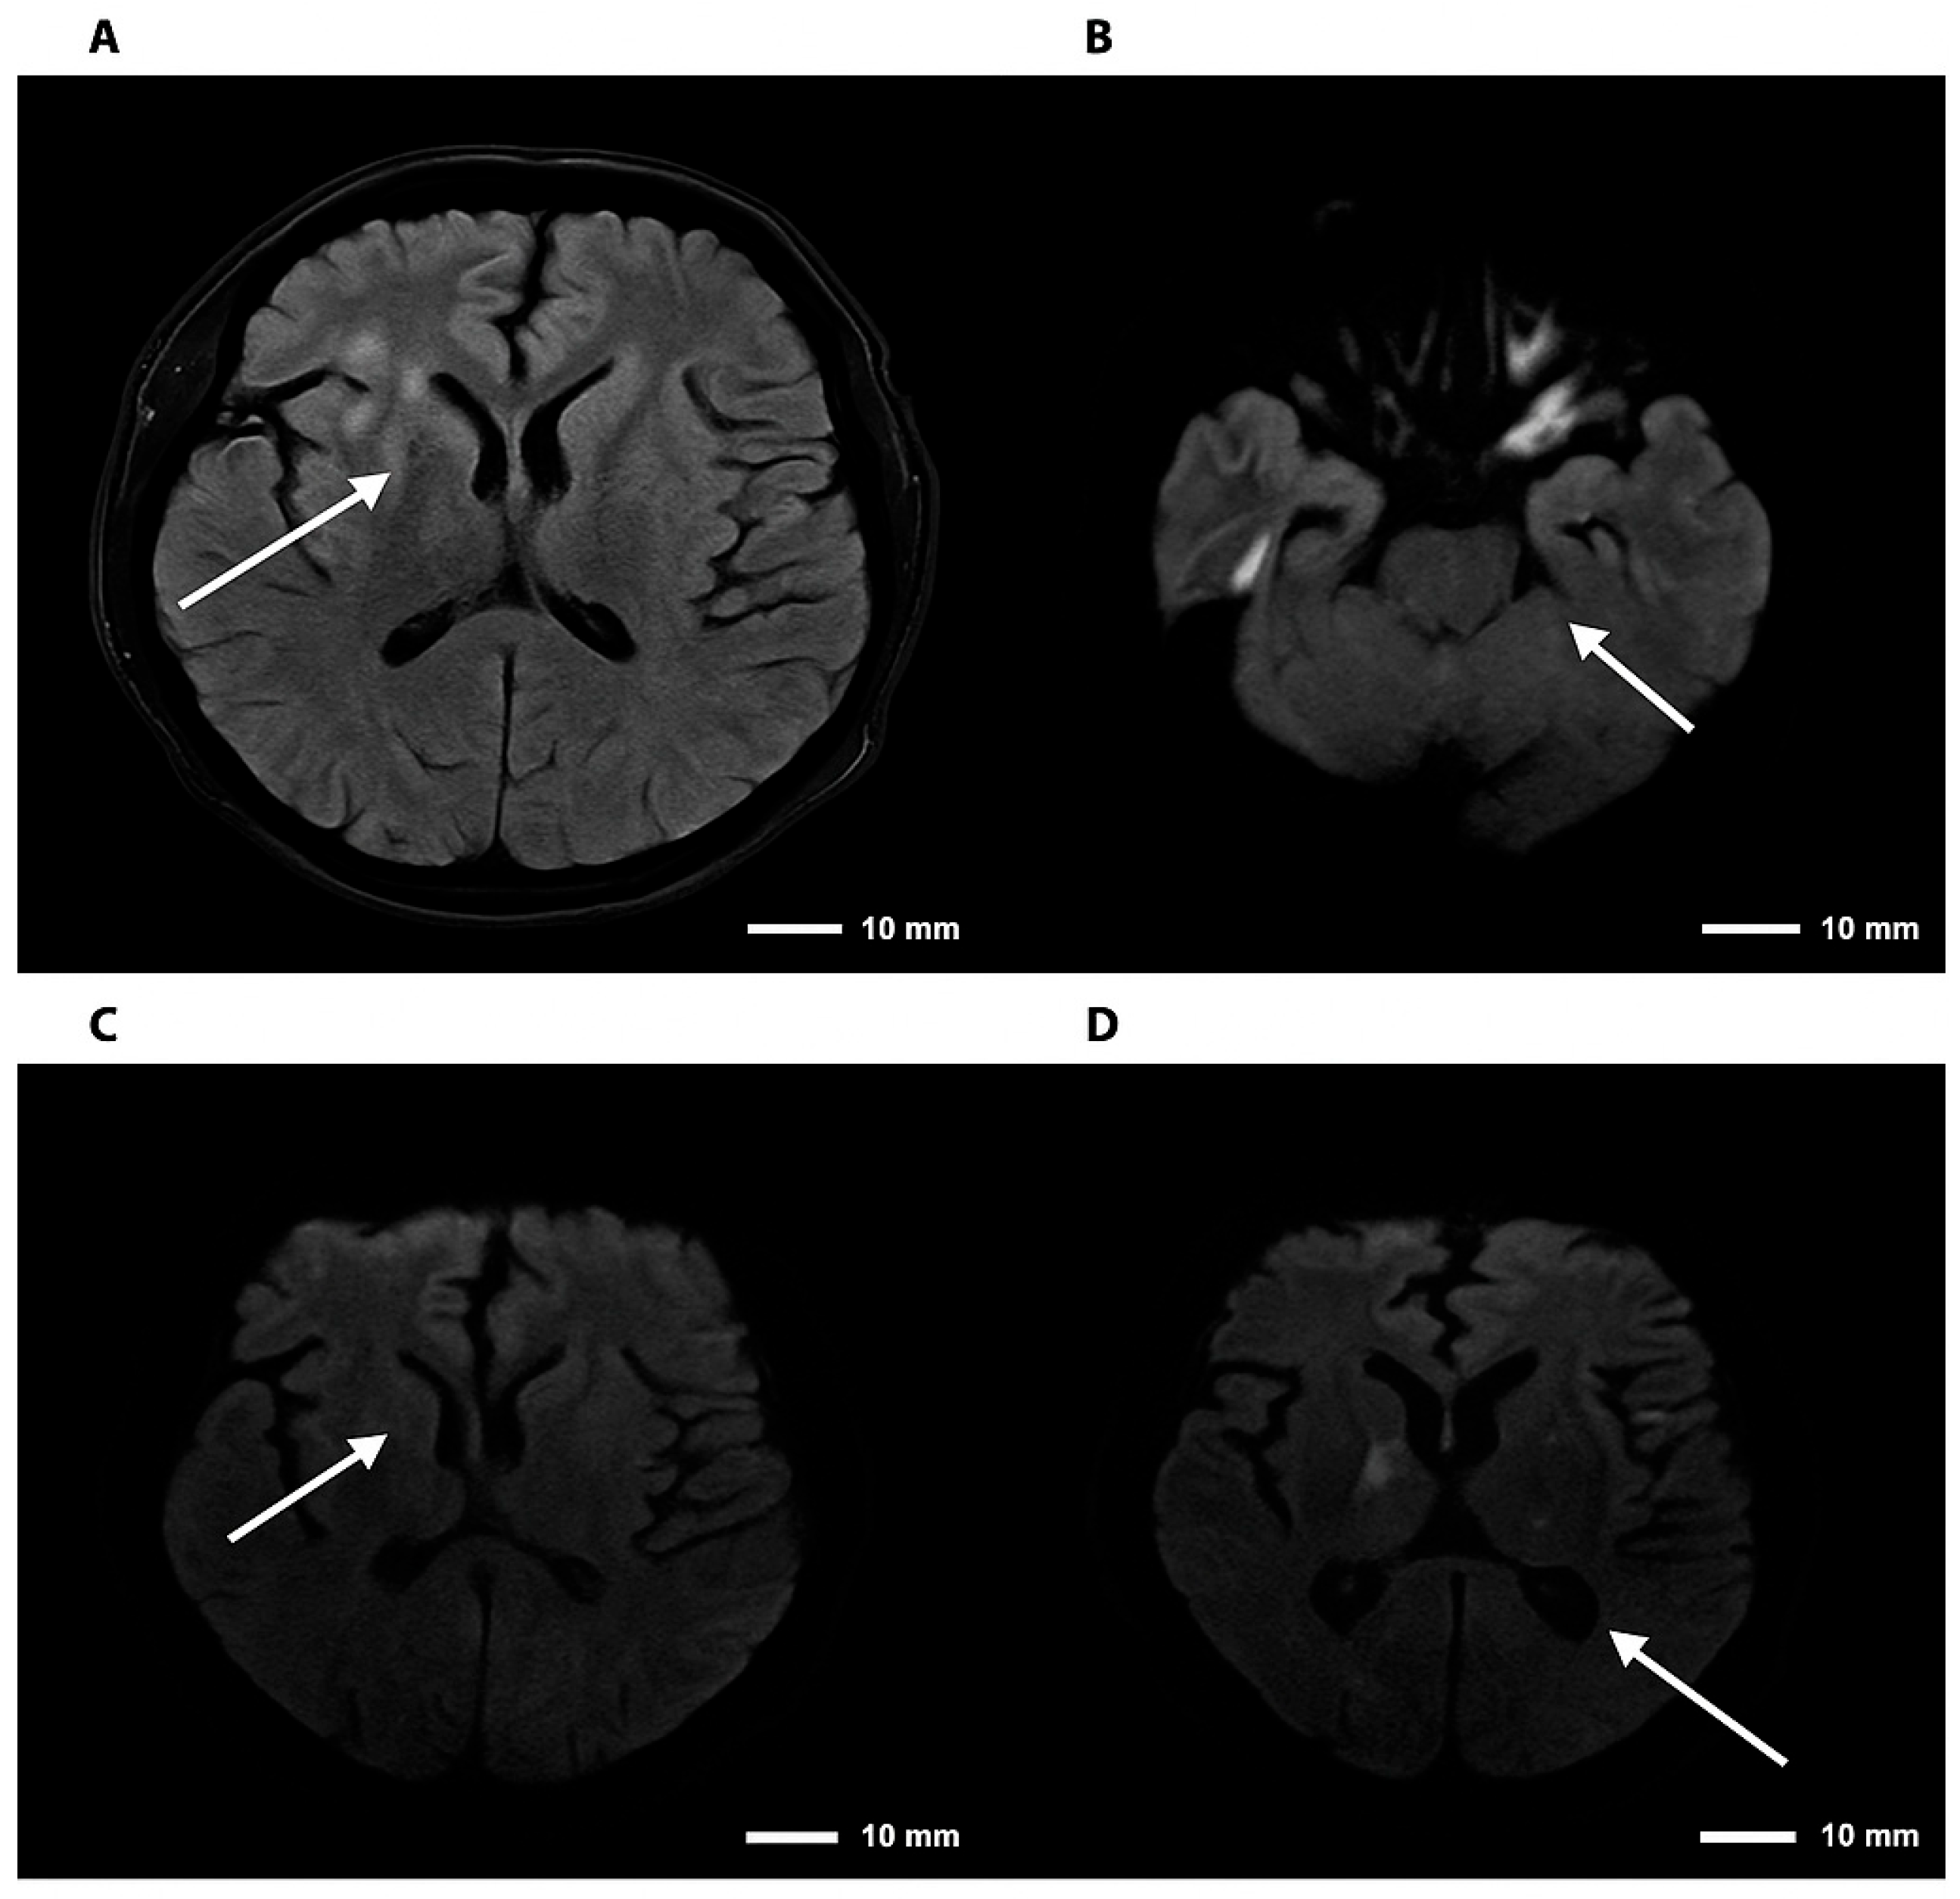

Figure 3.

Brain magnetic resonance imaging—FLAIR and DWI sequences in cryptococcal meningoencephalitis. Note. Brain magnetic resonance imaging. (A) Axial FLAIR sequence showing hyperintensity in the right basal ganglia. (B) DWI sequence demonstrating diffusion restriction in the right thalamic region. (C,D) Axial DWI images confirming foci of restriction in the right basal ganglia and thalamus, consistent with an infectious/inflammatory process. The arrows indicate lesions consistent with cryptococcomas, involving the supra- and infratentorial parenchyma to varying degrees.

Neuroimaging findings in CNS cryptococcosis are variable, with lesions mimicking tumors, ischemic events, or demyelination, emphasizing the need for integrating advanced imaging with molecular diagnostics for early and accurate detection [13,14].

The fact that the infection was predominantly localized in the cerebral parenchyma—evidenced by the focal hyperintense lesions in the thalamus and globus pallidus on MRI—and not in the subarachnoid space, may have resulted in a low concentration of antigen or fungal cells in the CSF. This localization in subcortical and limbic structures explains why atypical neuropsychiatric and cognitive manifestations predominated over classical meningeal signs, reinforcing the need to incorporate PCR into the diagnostic evaluation of acute neuropsychiatric syndromes in immunosuppressed patients.